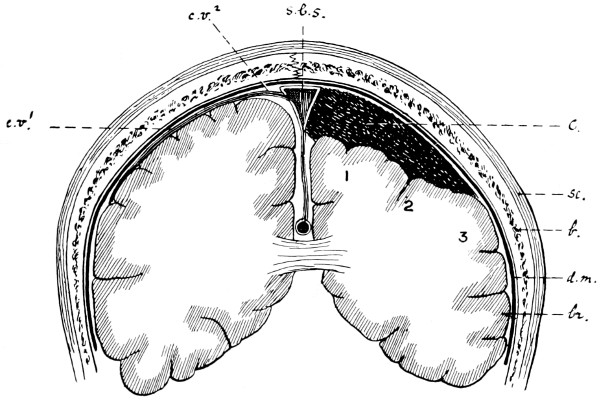

| 26. The author’s operation for Hydrocephalus internus | 64 |

| 27. The conversion of Hydrocephalus internus into cephalocele | 65 |